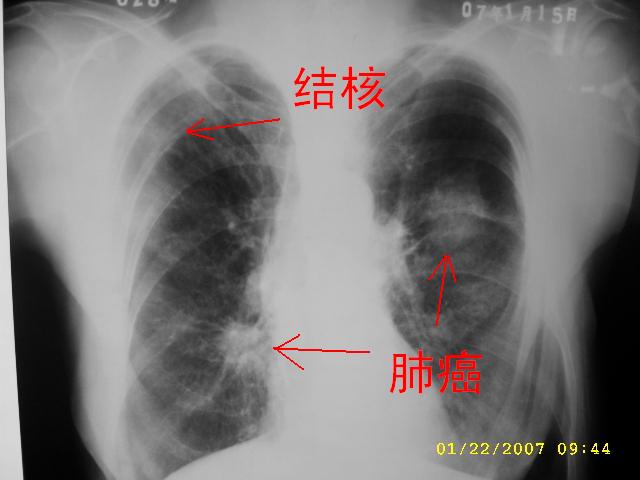

女,75.胸痛。

支持!另2007.1.15胸片还是显示有双肺的纤维条索状影,考虑合并有陈旧性肺结核。

明显的不规则形肿块,分叶、短毛刺、胸膜刺激征,血管扭曲征等周围型肺癌的征象明显,应首先考虑周围型肺癌。应与肺多发结核球相鉴别

双侧肺内块状病灶,均见分叶毛刺,左肺见典型胸膜凹陷,双侧双原发癌.

1.双肺上叶及右肺下叶结节,周围散在卫星灶,接近4年的病史,纵隔无肿大淋巴结,考虑结核

2.桶状胸,慢支,肺气肿